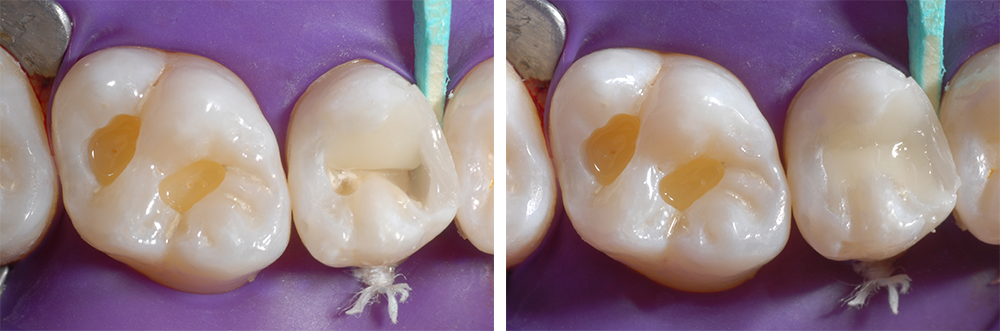

Ensuite, nous avons appliqué l’adhésif universel Futurabond U de VOCO, que nous avons ensuite polymérisé pendant 10 secondes (Ill. 7 et 8). À l’aide d’une matrice calée avec une clavette en bois, nous avons reconstitué la paroi proximale de la dent 15 avec une seule couche du matériau d’obturation nanohybride ORMOCER® Admira Fusion x-tra de VOCO, puis nous l’avons durcie pendant 20 secondes (Ill. 9 et 10).

Ill. 9 : Matrice fixée

Ill. 10 : Reconstitution de la paroi mésiale de la dent 15 avec une seule couche d’Admira Fusion x-tra

Deux autres couches ont été appliquées l’une après l’autre, côté palatin et côté vestibulaire, en tenant compte des détails importants du modelage occlusal anatomique, puis polymérisées séparément (Ill. 11 et 12). Avant le durcissement de la couche vestibulaire, le sillon central de la dent 15 a été modelé à l’aide d’une sonde fine (Ill. 13).

Ill. 14 : Obturation des cavités au niveau de la dent 16 avec une seule couche par cavité

Nous avons restauré la dent 16 à l’aide de la technique adhésive, avec une seule couche par cavité (Ill. 14).